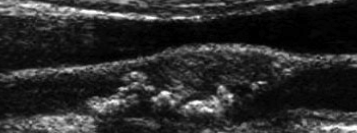

what are teh 5 carotid plaque types, characteristics and risk of symptoms?

what type of plaqe is shown here?

smooth plaque

what type of plaque is this

irregular, complex. older, has been there longer b/c hyperechoic